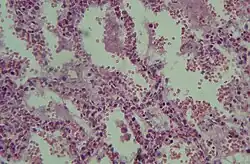

Diese akute respiratorische Insuffizienz wird beim akuten Lungenversagen durch eine schwere diffuse Schädigung des Lungenparenchyms verursacht. Weitere Komponenten sind Perfusionsstörungen, Gerinnungsstörungen, Permeabilitätsstörungen der Alveolarwände, Lungenödem, Abbau von Surfactant und bindegewebiger Umbau von Lungengewebe.

Das ARDS verläuft für gewöhnlich in drei Phasen: der exsudativen Phase, der frühen und der späten proliferativen Phase.